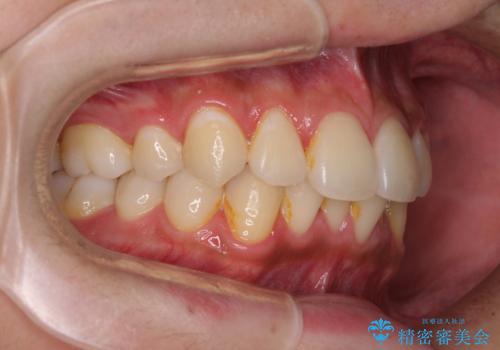

- 30代男性

- インビザライン・ライト

- 9ヶ月

- 5-10回

- 治療費の目安: 50万円(税込)費用は治療当時の料金となります